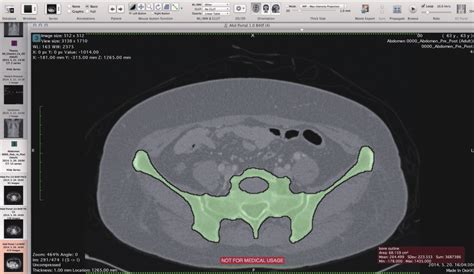

Osirix is an open-source DICOM viewer, and image processing software specifically designed for medical images. DICOM, which stands for Digital Imaging and Communications in Medicine, is the standard for handling, storing, printing, and transmitting information in medical imaging. Osirix is primarily used in the medical field by radiologists, surgeons, and other healthcare professionals to visualize and analyze medical images, such as those obtained from CT scans, MRI scans, PET scans, and ultrasound. This powerful tool offers a range of features, including 2D and 3D visualization, image reconstruction, and advanced analysis tools, making it an indispensable asset in modern medical diagnostics and treatment planning. Osirix distinguishes itself through its user-friendly interface, robust functionality, and the fact that it is open-source, allowing for continuous development and customization by a global community of users. Its capabilities extend to image registration, fusion, and segmentation, further enhancing its utility in complex clinical scenarios. Whether for routine diagnostics or advanced research, Osirix provides a comprehensive platform for medical image analysis, contributing significantly to improved patient care and outcomes. Radiologists and other medical professionals leverage Osirix to enhance their diagnostic accuracy and streamline their workflows. The software’s intuitive design allows for easy navigation and manipulation of complex datasets, enabling clinicians to quickly identify and assess critical anatomical structures and pathological conditions. Furthermore, the ability to customize Osirix through plugins and extensions means that healthcare providers can tailor the software to meet their specific needs and research interests. The open-source nature of Osirix also fosters collaboration and knowledge sharing among users, leading to continuous improvements and innovations in medical imaging analysis. In essence, Osirix embodies the principles of accessible, cutting-edge technology, empowering healthcare professionals to deliver the best possible care to their patients. With its widespread adoption and ongoing development, Osirix remains at the forefront of medical imaging software, shaping the future of diagnostics and treatment in healthcare systems worldwide.

In Indonesia, Osirix is gaining traction as a vital tool in hospitals, clinics, and research institutions. Its open-source nature makes it an attractive option for healthcare providers seeking cost-effective solutions without compromising on functionality. Indonesian radiologists and clinicians use Osirix for a variety of purposes, including visualizing CT scans, MRI scans, and other medical images to diagnose diseases, plan surgeries, and monitor treatment progress. The software’s advanced features, such as 3D reconstruction and image fusion, enable healthcare professionals to gain a comprehensive understanding of complex anatomical structures and pathological conditions. Moreover, Osirix’s compatibility with DICOM standards ensures seamless integration with existing imaging equipment and PACS (Picture Archiving and Communication System) networks, facilitating efficient workflow management. The adaptability of Osirix to different clinical settings and its ability to be customized through plugins make it a valuable asset for Indonesian healthcare providers. Training programs and workshops are being conducted to equip medical professionals with the skills needed to effectively utilize Osirix in their daily practice. The adoption of Osirix in Indonesia is not only improving diagnostic accuracy and treatment outcomes but also fostering collaboration and knowledge sharing among healthcare professionals. As more institutions embrace this powerful imaging software, the standard of medical care in Indonesia is expected to rise, benefiting patients across the archipelago. The accessibility of Osirix, coupled with its robust functionality, makes it an ideal solution for addressing the diverse healthcare needs of the Indonesian population. In remote areas where access to specialized medical expertise may be limited, Osirix can be used to transmit medical images to specialists in urban centers for remote diagnosis and consultation. This telemedicine approach can significantly improve healthcare access and reduce disparities in health outcomes between urban and rural communities. Furthermore, Osirix is playing a crucial role in medical research in Indonesia, enabling scientists and clinicians to analyze medical images and identify patterns that can lead to new insights into disease mechanisms and treatment strategies. By empowering healthcare professionals and researchers with advanced imaging tools, Osirix is contributing to the advancement of medical knowledge and the improvement of patient care in Indonesia.

Osirix provides advanced visualization tools, including 3D reconstruction, multi-planar reconstruction (MPR), and volume rendering. These features enable healthcare professionals to visualize anatomical structures and pathological conditions in great detail, leading to more accurate diagnoses and better treatment planning. In a country like Indonesia, where access to specialized medical expertise may be limited in certain regions, the ability to visualize complex medical images remotely can be invaluable. Osirix’s advanced visualization capabilities allow specialists in urban centers to review and interpret images from remote healthcare facilities, providing timely consultations and guidance to local healthcare providers. This telemedicine approach can significantly improve healthcare access and reduce disparities in health outcomes between urban and rural communities. Furthermore, Osirix’s advanced visualization tools are essential for surgical planning and navigation. Surgeons can use the software to create detailed 3D models of anatomical structures, allowing them to visualize the surgical site and plan their approach with greater precision. This can lead to shorter surgical times, reduced complications, and improved patient outcomes. In addition to its clinical applications, Osirix’s advanced visualization capabilities are also valuable for medical research and education. Researchers can use the software to analyze medical images and identify patterns that can lead to new insights into disease mechanisms and treatment strategies. Medical educators can use Osirix to create interactive learning modules that allow students to explore anatomical structures and pathological conditions in a virtual environment. The versatility of Osirix’s advanced visualization tools makes it an indispensable asset for healthcare professionals, researchers, and educators in Indonesia.